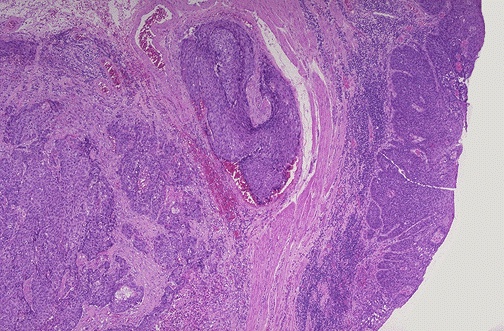

Image 1.3

The low power microscopic appearance of the mid-esophageal mass lesion is seen here.